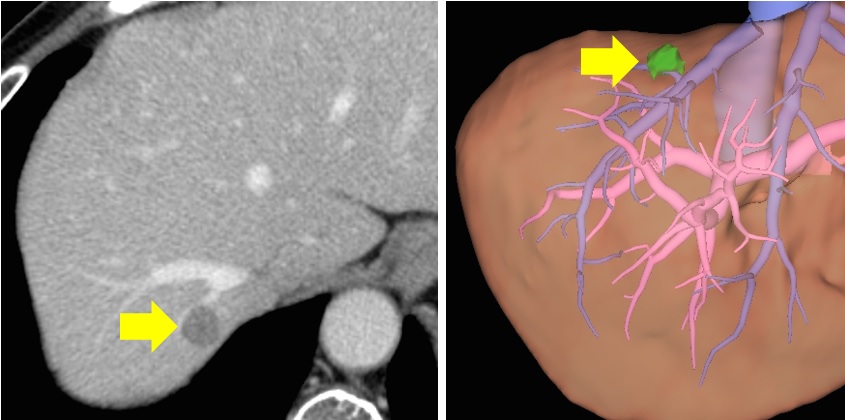

(4) 간암

간암은 간세포에서 발생하는 악성 종양으로, 일반적으로 간염이나 간경변과 관련이 깊습니다. 증상으로는 다음과 같은 것들이 있습니다.

- 체중 감소

- 식욕 부진

- 오른쪽 복부의 통증

- 피로감